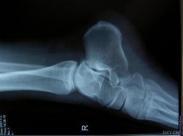

跟腱断裂

跟腱是人体内最粗、最强大的肌腱,长约15cm,它位于小腿下段后方,连接小腿三头肌和跟骨,其主要功能是负责踝关节的跖屈,对于行走、跑步、跳跃等动作的完成起着重要作用。跟腱断裂后患者的行走功能将受到严重影响。跟腱断裂常见于运动中。